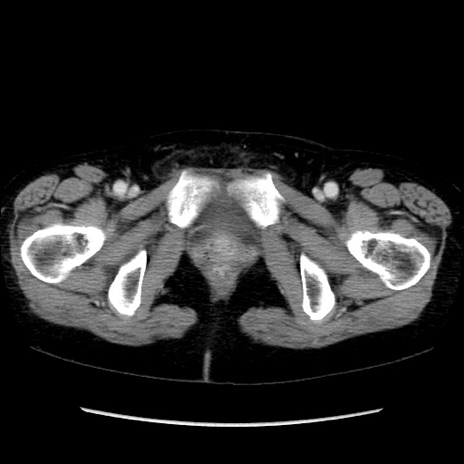

【症例】40歳代 女性

【主訴】上腹部痛、嘔気・嘔吐

【現病歴】約9時間前頃から急に上腹部痛、嘔気、嘔吐が出現。改善しないため救急要請。

【既往歴】子宮頚癌(広汎子宮全摘術、放射線療法)、腸閉塞

【身体所見】腹部:平坦、軟、腸雑音亢進、上腹部を中心に腹部全体に圧痛あり。

【データ】WBC 8400、CRP 0.03